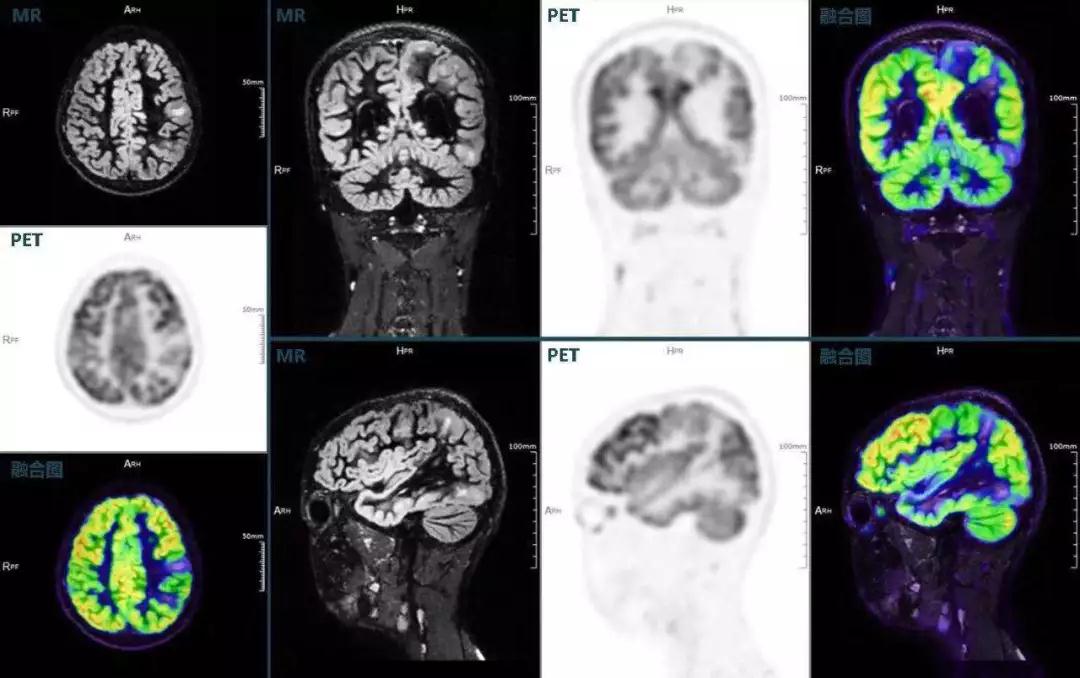

癲癇

不僅如此,聯(lián)影“時空一體”超清TOF PET/MR還搭載了大量可用于神經(jīng)疾病領(lǐng)域的高級應用,如DIR(Double Inversion Recovery雙反轉(zhuǎn)恢復)序列能夠清晰顯示大腦皮層的結(jié)構(gòu)成像,對于皮層腫脹,膠質(zhì)增生等癲癇的影像征象都能清楚呈現(xiàn);DTI(Diffusion Tensor Imaging彌散張量成像)高級應用能夠顯示細小的神經(jīng)纖維束缺損,以更加定量的形式為醫(yī)生提供一個全新的診斷維度,輔助醫(yī)生精準診斷。

(結(jié)節(jié)性硬化,MR DIR序列清晰顯示腦皮層病理改變,PET顯示了病灶區(qū)域FDG的低濃聚。PET/MR融合顯像同時提供了結(jié)構(gòu)異常改變和功能變化的信息。)